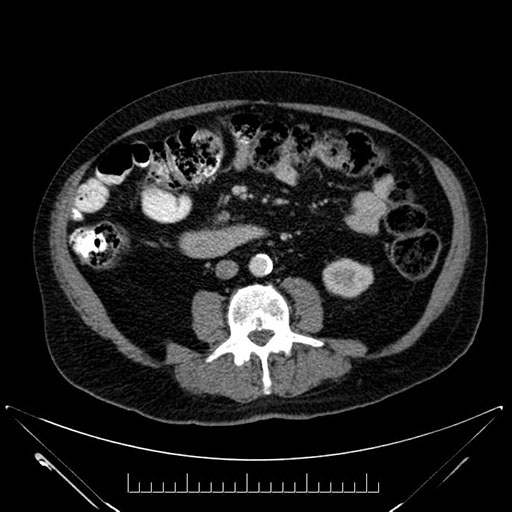

Axial - stented